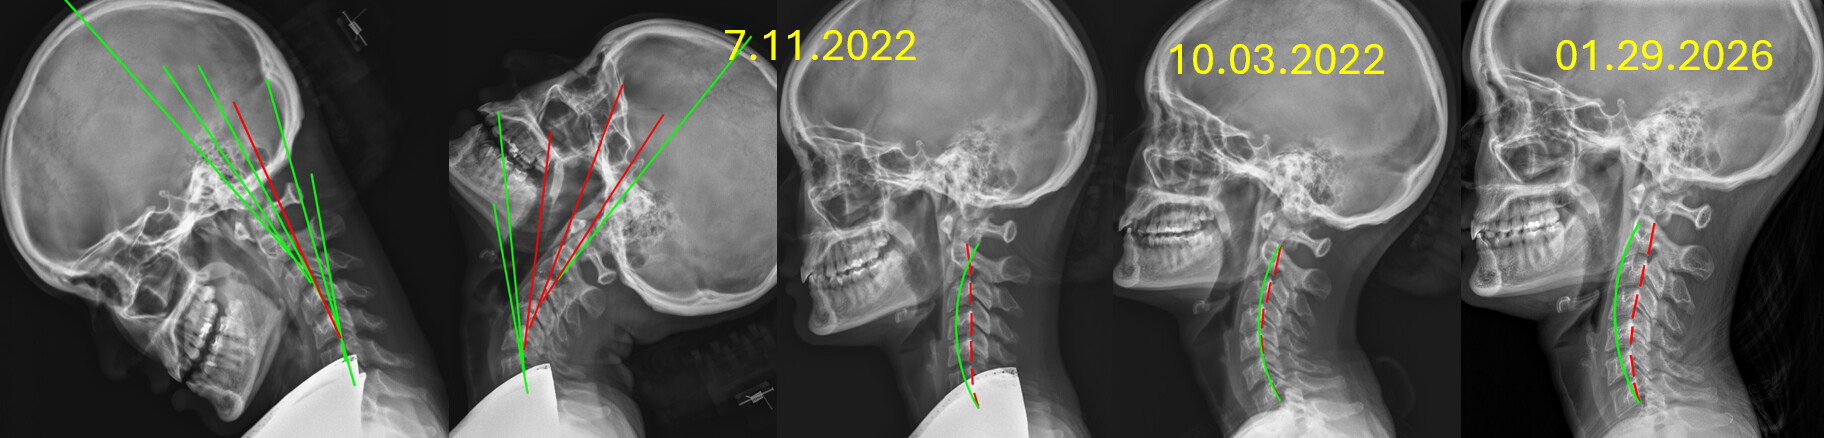

13 Month follow up images in our office.